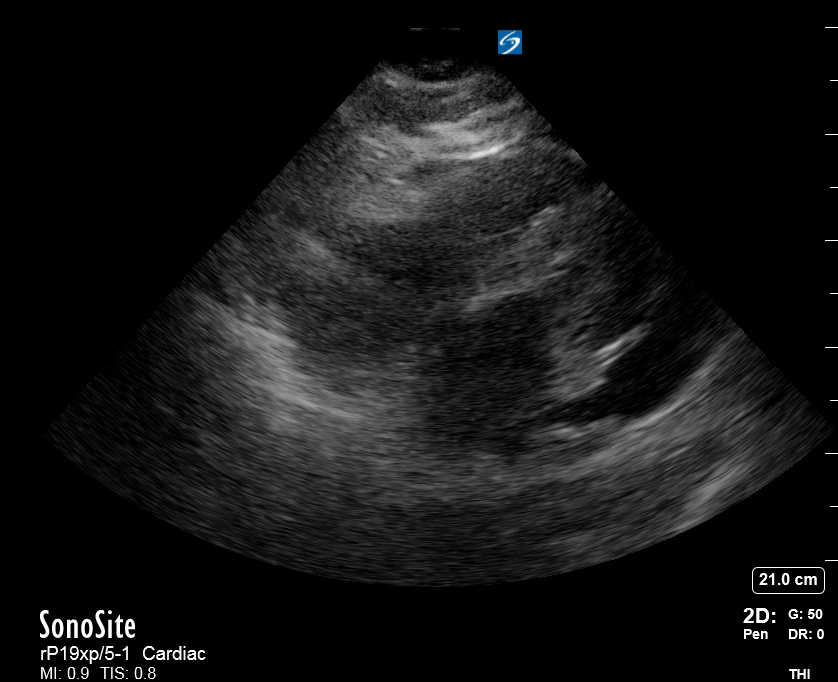

THE VIEWS

The subxiphoid view is the most reliable for detecting pericardial effusion. Still, it is ideal to obtain different views not to miss a focal effusion as small amounts of fluid can lead to tamponade physiology. Tamponade does not link strictly to the size of the effusion, but correlates more with the speed of onset, causes, and haemodynamic effects.

PITFALLS & PLEURAL EFFUSIONS

A common error is to confuse a pericardial fat pad with effusion. Fatty tissue has a heterogeneous echotexture, moving in coordination with the myocardium, and it cannot be tracked around the heart, especially posteriorly and to the apex. Another pitfall is misinterpreting a pleural effusion as a pericardial effusion. However, they can be differentiated by their relationship to the descending aorta. Pericardial effusion may be seen between the aorta and the LV free wall, whereas pleural effusions are posterior to the descending aorta. Lastly, other causes, namely hypovolaemia and large pleural effusions, can cause RA and RV collapse.